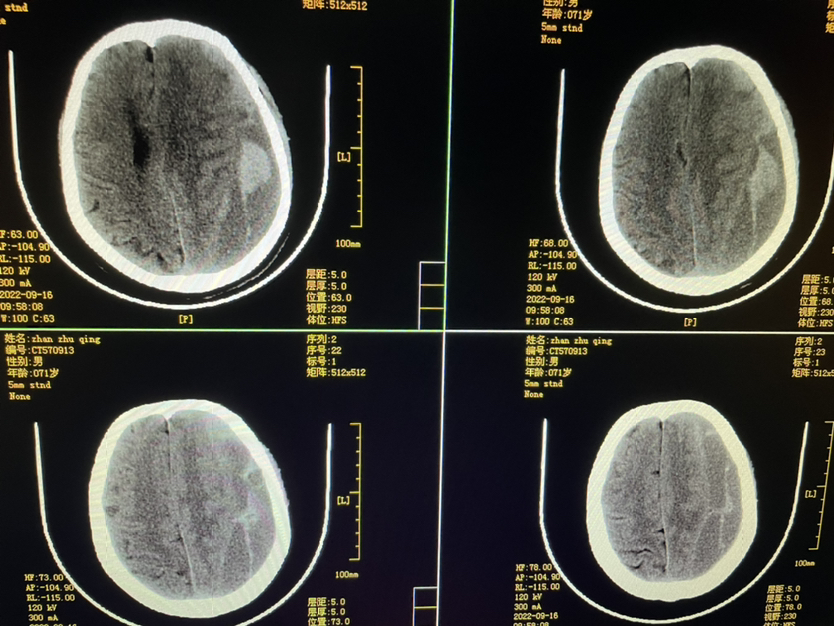

448859,头疼四肢乏力4天,71y